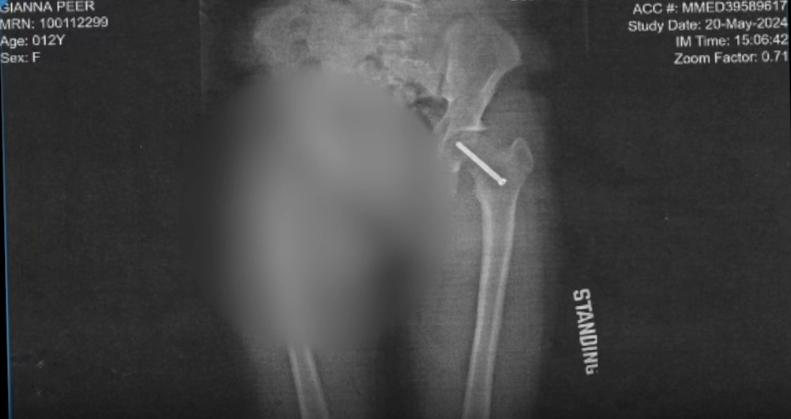

The Peer family went to a doctor. Gianna was instantly diagnosed with SCFE, which stands for Slipped Captial Femoral Epiphysis.

"The femur of the left leg when she ran would slide out of the hip socket, in and out, and (she) never complained about the pain," Jeff said.

Within a day of diagnosis, Gianna had surgery in Ann Arbor, and got a screw in her hip.